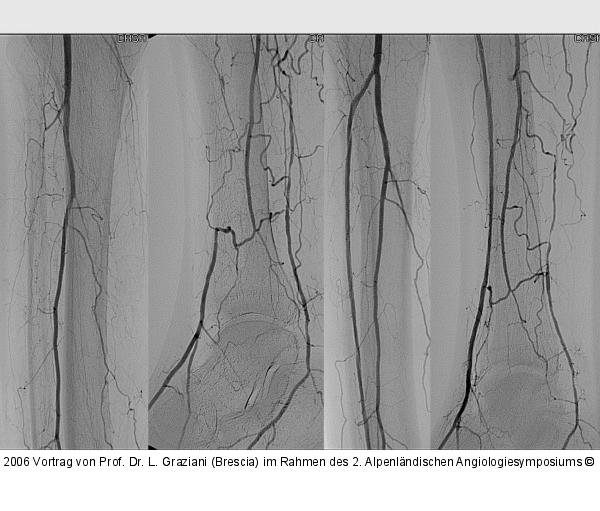

Vortrag von Prof. Dr. L. Graziani (Brescia) im Rahmen des 2. Alpenländischen Angiologiesymposiums

PTA of the foot arteries in diabetics: Extremities Extreme Angioplasty

Abbildung 37: PTA